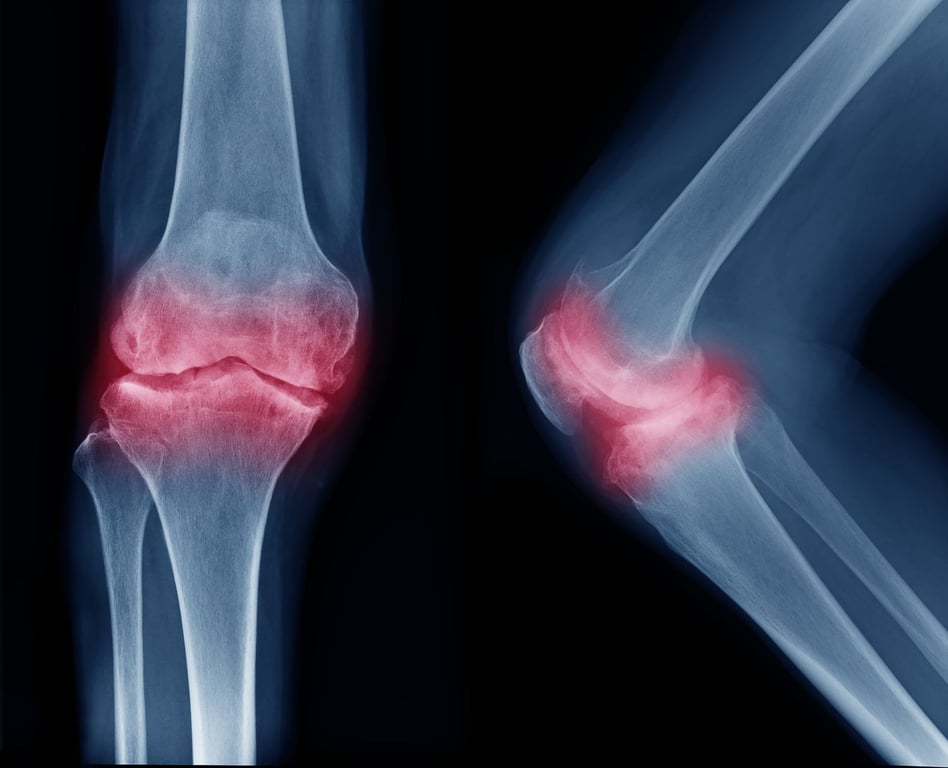

New Biomaterial May Help Regrow Cartilage in Damaged Joints